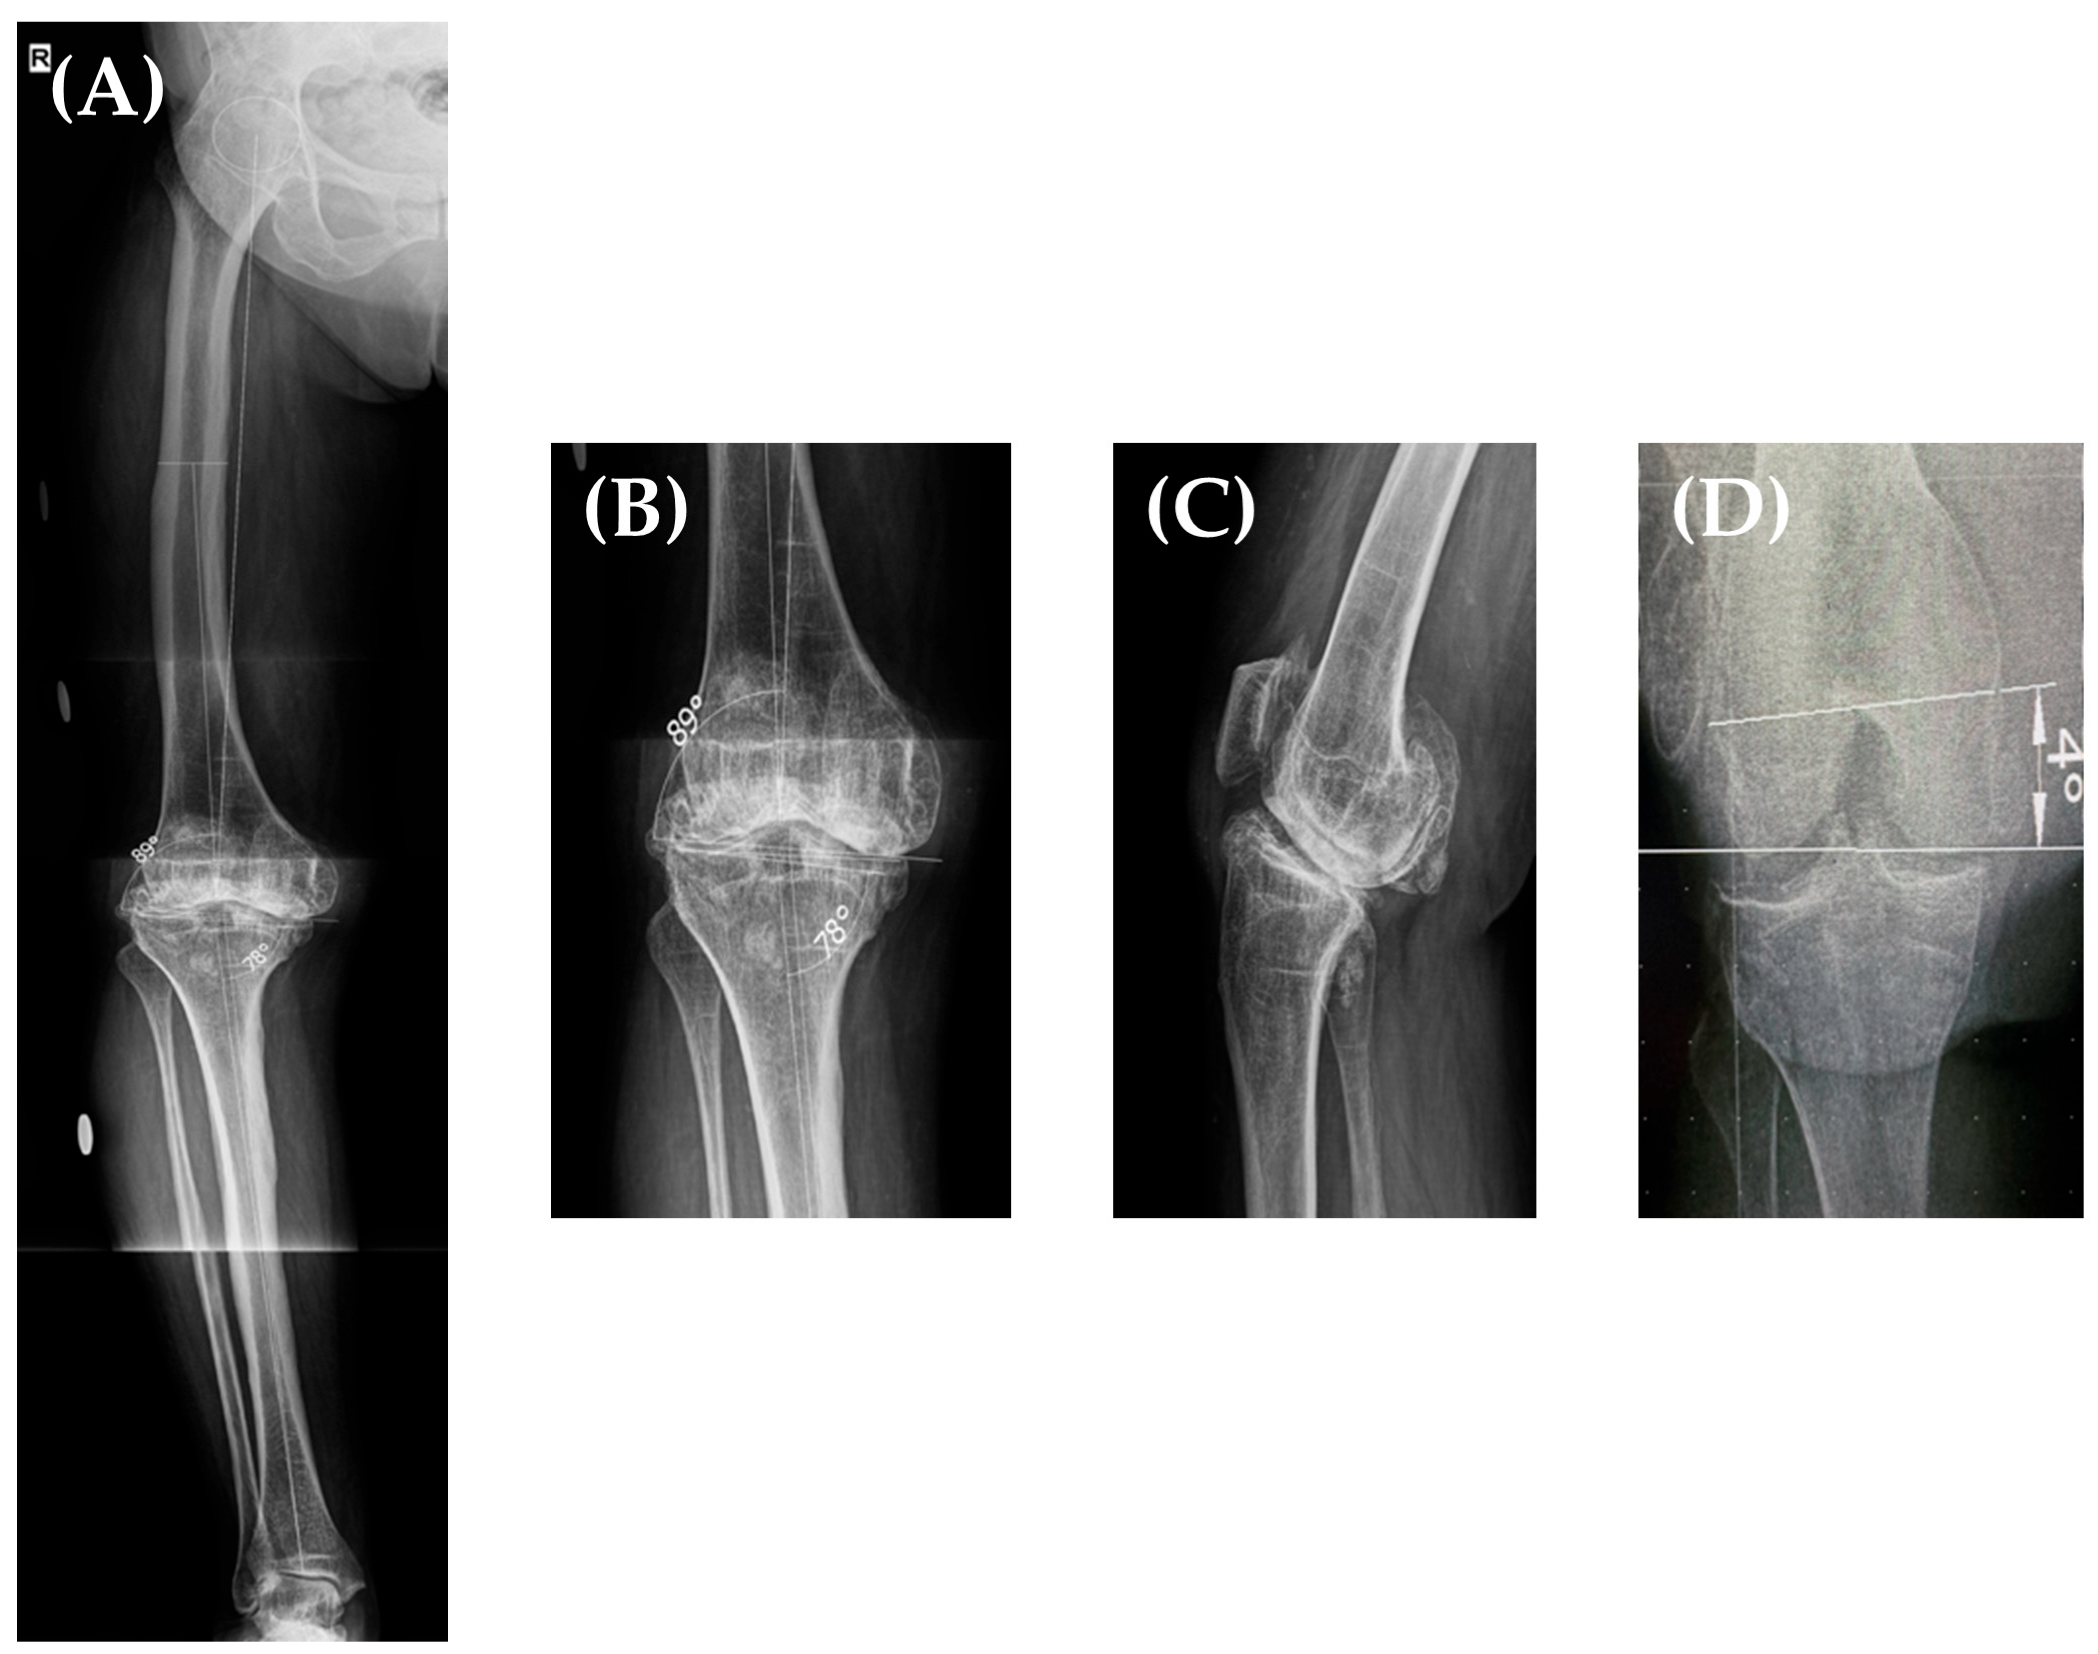

In 2018, a 75-year-old female patient who underwent right hip fusion at the age of 15 due to bacillary osteoarthritis was admitted to our clinic. She complained of severe pain and a significantly decreased range of motion (ROM) in her right (ipsilateral) knee; the patient was ambulating with the aid of crutches. The clinical examination of her right knee (Figure 1) revealed a right knee flexion of 90°, a 15° flexion contracture, and no mediolateral ligamentous instability. Her fused right hip was fixed in a flexion of 15°–20°, neutral abduction/adduction, and neutral internal/external rotation; she did not report any pain/discomfort in this hip. Her leg length discrepancy was measured at 3 cm, and she compensated for it with custom insoles.

Taking all of this into account, we decided to perform a total knee arthroplasty on her right knee. Her preoperative planning long leg X-ray (Figure 3A,B) showed a grade II varus deformity of 12° (Hip-Knee-Angle—HKA of 168°), a lateral distal femoral angle (LDFA) of 89°, and a medial proximal tibial angle (MPTA) of 78° [13] with an increased posterior tibial slope and an IM angle (the angle between the femoral anatomical and mechanical axis) of 6°. Furthermore, in our clinic, we routinely perform a “seated view” X-ray which, according to our previous studies [14], helps in determining the distal femoral torsion. Using this special X-ray, where the patient sits on a radiolucent support with the knee flexed at 90°, we determine the posterior condyle angle (PCA) (and thus, the distal femoral rotation) by measuring the angle between the femoral trans-epicondylar axis (a line from the lateral epicondyle connecting it to the sulcus of the medial epicondyle) and the line connecting the posterior femoral condyles (Figure 3D); in this case, the femoral torsion was determined to be 4°.

Figure 1. Right hip fusion, with the hip fused in 15° HF (A), neutral HA, and neutral HER (B). Right knee flexion of 90° (C) and 10° of flexion contracture (D).